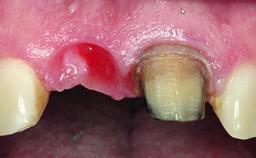

A healthy 37-year-old female patient was referred for a consultation on the replacement of missing tooth 21 with an implant-supported restoration. She stated that several years previously the tooth had been traumatically avulsed following a motor vehicle accident. The tooth was replaced with a three-unit fixed partial denture (FPD) immediately afterwards. Over time, she became disillusioned with the FPD and looked for a different option, including orthodontic therapy. She presented still in her orthodontic appliances, with the pontic sectioned free from the FPD but attached to the archwire. Her orthodontist felt that orthodontic treatment had been successfully completed, but nevertheless referred her before removing the appliances in case adjustments were necessary.

Soft Tissue Grafting Simultaneous

Bone Volume Deficient horizontally, allowing simultaneous augumentation

Soft Tissue Contour and Volume Slightly compromised